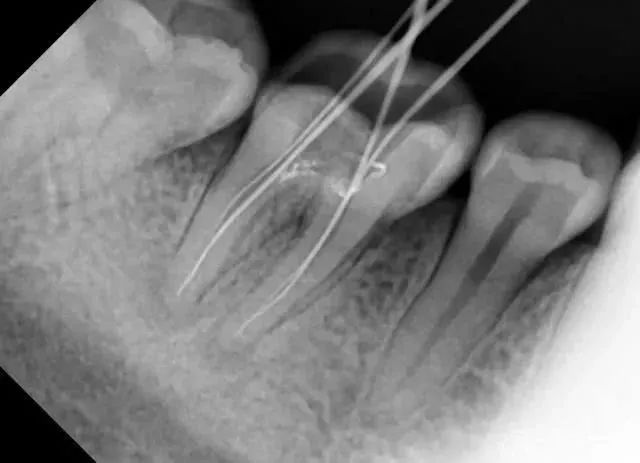

例如,當拔低頜智慧齒嘅時候,只憑口內檢查唔到佢嘅神經管位置

線片x線片唔止可以明白牙齒本身嘅病變情況,還可以明白牙根下有冇囊腫、周圍骨頭有冇吸收以及牙槽骨入面有冇埋伏牙、多生牙等。依據X線片綜合分析,可以提高齒科醫生診斷治療牙齒嘅準確性同成功率。

醫生想判斷牙床骨係咪適合種植條件,或者了解埋伏嘅阻生齒嘅三維位置同埋其他頜骨內嘅病變組織嘅形態同大小時,就需要進一步影相 CBCT 。

所以,影牙片係一種幫助牙科醫生進行診斷、治療、療效評估嘅重要手段,治療前用於發現病變程度、範圍;治療中用於引導治療、確定治療範圍和深度;治療後用於觀察療效。